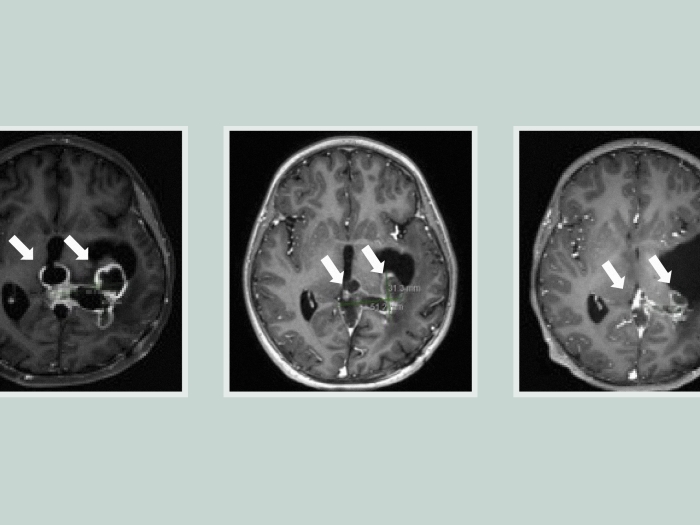

Study finds improved survival for incurable brain tumor, providing ‘a crack in the armor’

A potential drug candidate called ONC201 nearly doubled survival for patients with diffuse midline glioma and DIPG.